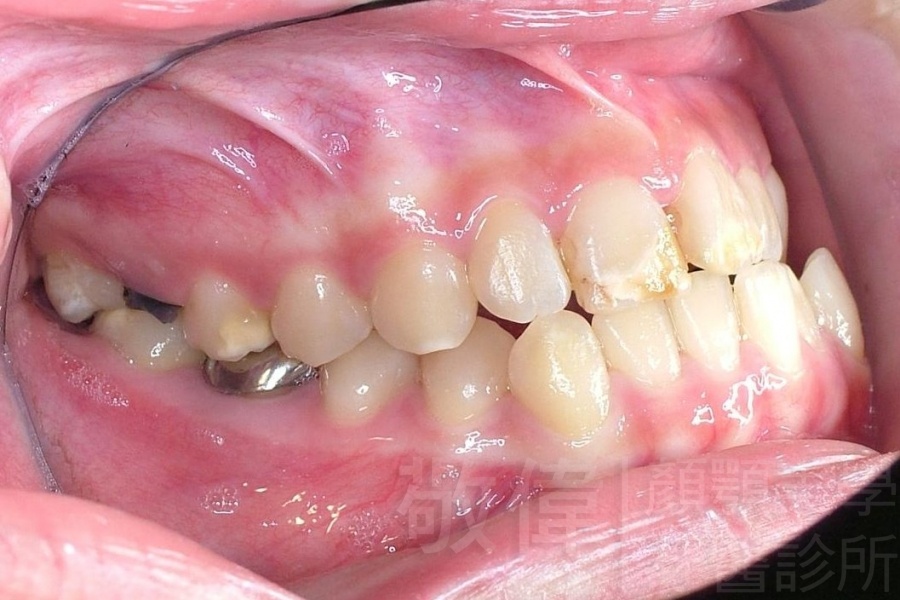

齒顏矯正/戽斗、亂牙、爛牙,變身 免植牙的健牙美女

<個案說明>

變臉矯正,原來戽斗妹跟大歪臉變成自信正妹

經由本院3D數影X光影像儀分析、與3D齒顎顏矯正技術,再配合口腔顎面正顎專科醫師施以正顎手術治療,雙方共同合作,使患者臉部外觀有很好的改善,大歪變小歪,產生了天南地北的大改變,她的人生也整個變得不一樣。